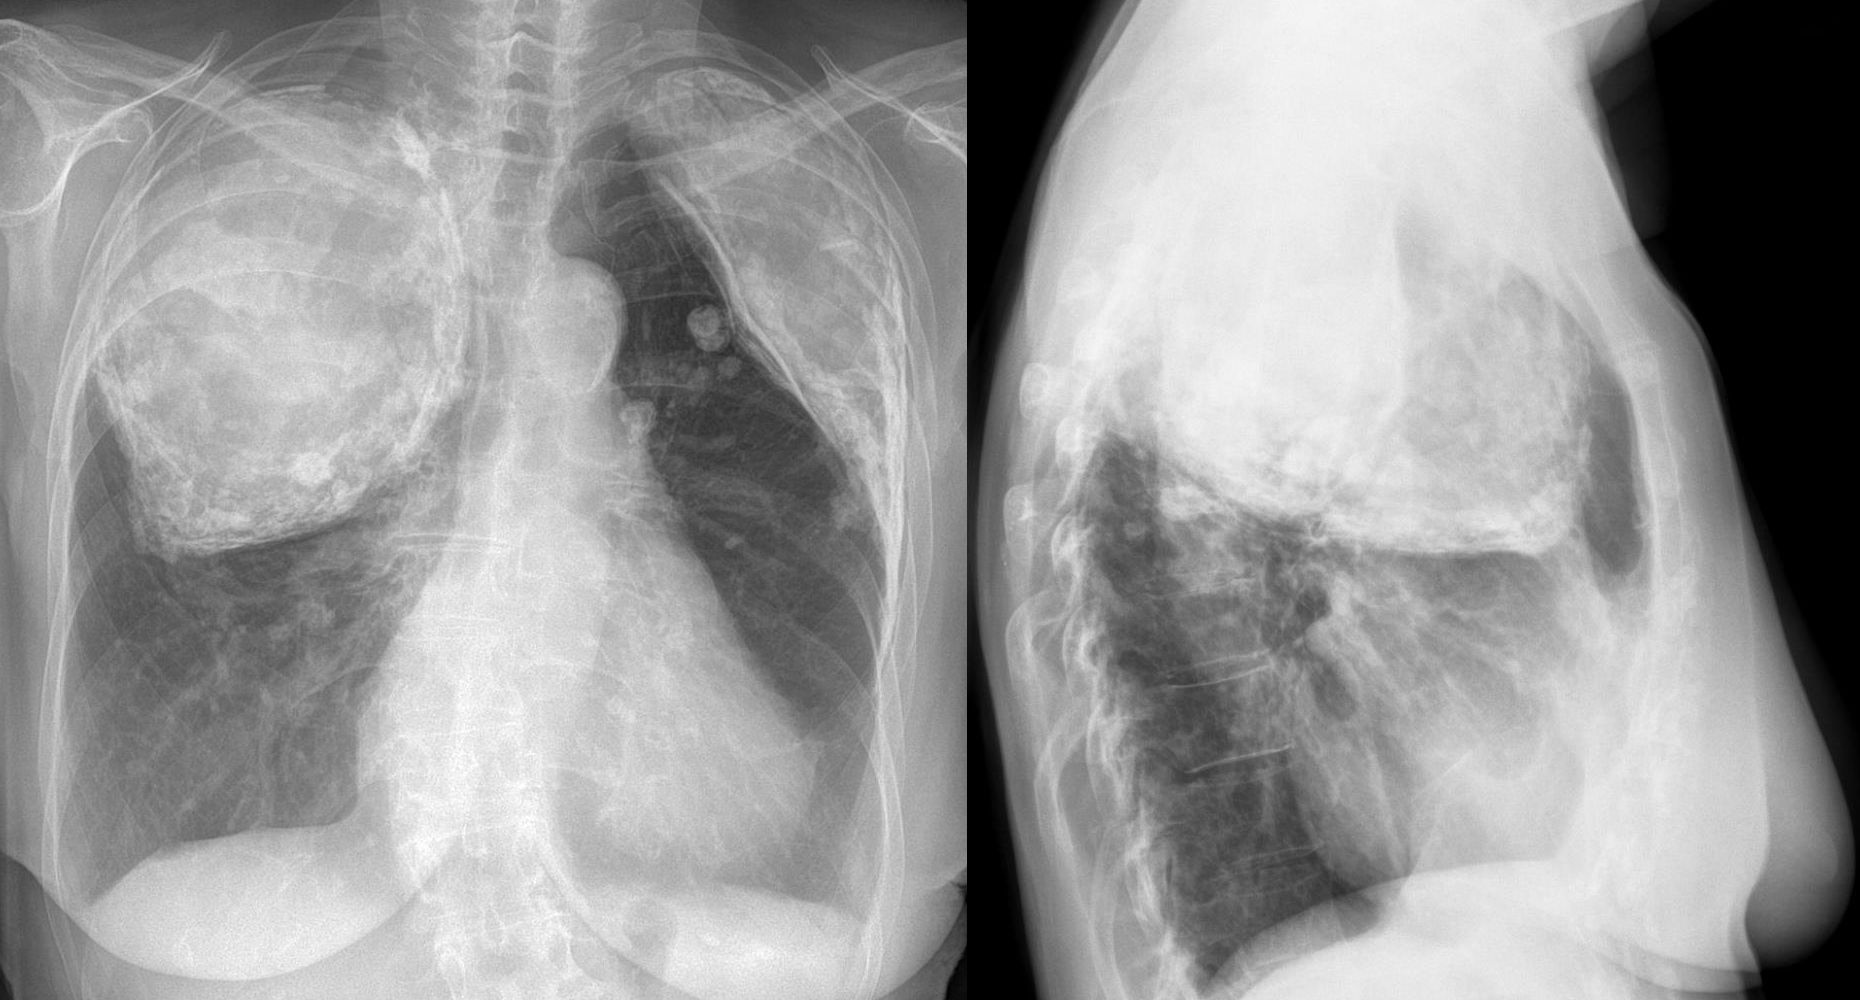

Prima dell'introduzione di una medicina contro la tubercolosi, la pleumonolisi era utilizzata per affrontare il malanno, tra gli anni '30 e i '50. Si trattava di far collassare un polmone creando una cavità sotto le costole superiori. Si credeva che un polmone collassato potesse guarire più velocemente. Ovviamente anche questa era una pratica che creava soltanto complicazioni.